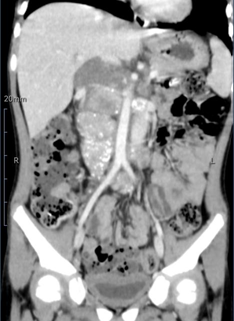

经过检查和诊断,医生发现小喜腹腔里的肿瘤不仅非常大,而且有骨髓转移的迹象,肿瘤包绕着腹主动脉、下腔静脉、肾动静脉等多条重要血管,小喜处于神经母细胞瘤Ⅳ期,失去了手术机会。

随后小喜顺利接受了四个疗程的化疗,庆幸的是,小喜的化疗效果非常好,不仅能耐受化疗的副作用,而且 4 月的腹部 CT 复查结果显示肿瘤明显缩小,这场与死神的较量终现曙光。

4 月 15 日,小喜被推进了手术室。随着手术的进行,肿瘤赫然入目,医生发现情况与术前分析预估的一致:肿瘤位于脊柱体右缘,下腔静脉被推挤并部分包绕,腹主动脉及其发出的肾动脉血管深不可见…… 经过 7 个多小时的努力,医生终于顺利地将小喜体内的肿瘤完全摘除,同时清扫了腹主动脉旁转移的淋巴结。